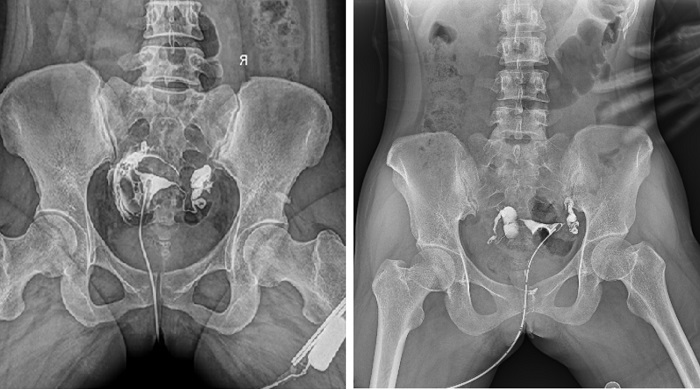

輸卵管造影檢查可根據(jù)造影劑在輸卵管及盆腔內的顯影情況了解輸卵管是否通暢、阻塞部位及宮腔形態(tài),是超聲、CT、核磁、宮腔鏡、腹腔鏡、輸卵管鏡等所無法替代的。作為目前普放領域最先進的影像設備,多功能動態(tài)DR進行子宮輸卵管造影檢查,大大超越了過去的檢查技術,更加精準、便捷、高效。

相較于傳統(tǒng)胃腸機,動態(tài)DR矩形采集面積大,一次曝光即可顯示整個盆腔,大幅減少觀察時間,可控的瞬時照射避免受檢者吸收過多的X線,對育齡期女性的檢查尤為重要。毫秒級時間內高清點片,可以在造影劑流動的過程中完成拍片,抓拍到關鍵圖像,更加清楚地了解到管腔的具體通暢情況及堵塞部位,對檢查及診斷有非常重要的價值。

子宮輸卵管造影

此外,應用動態(tài) DR 進行子宮輸卵管造影,還可以在加壓推注下,使部分輸卵管輕、中度堵塞的患者得以通暢,起到一定的治療作用。